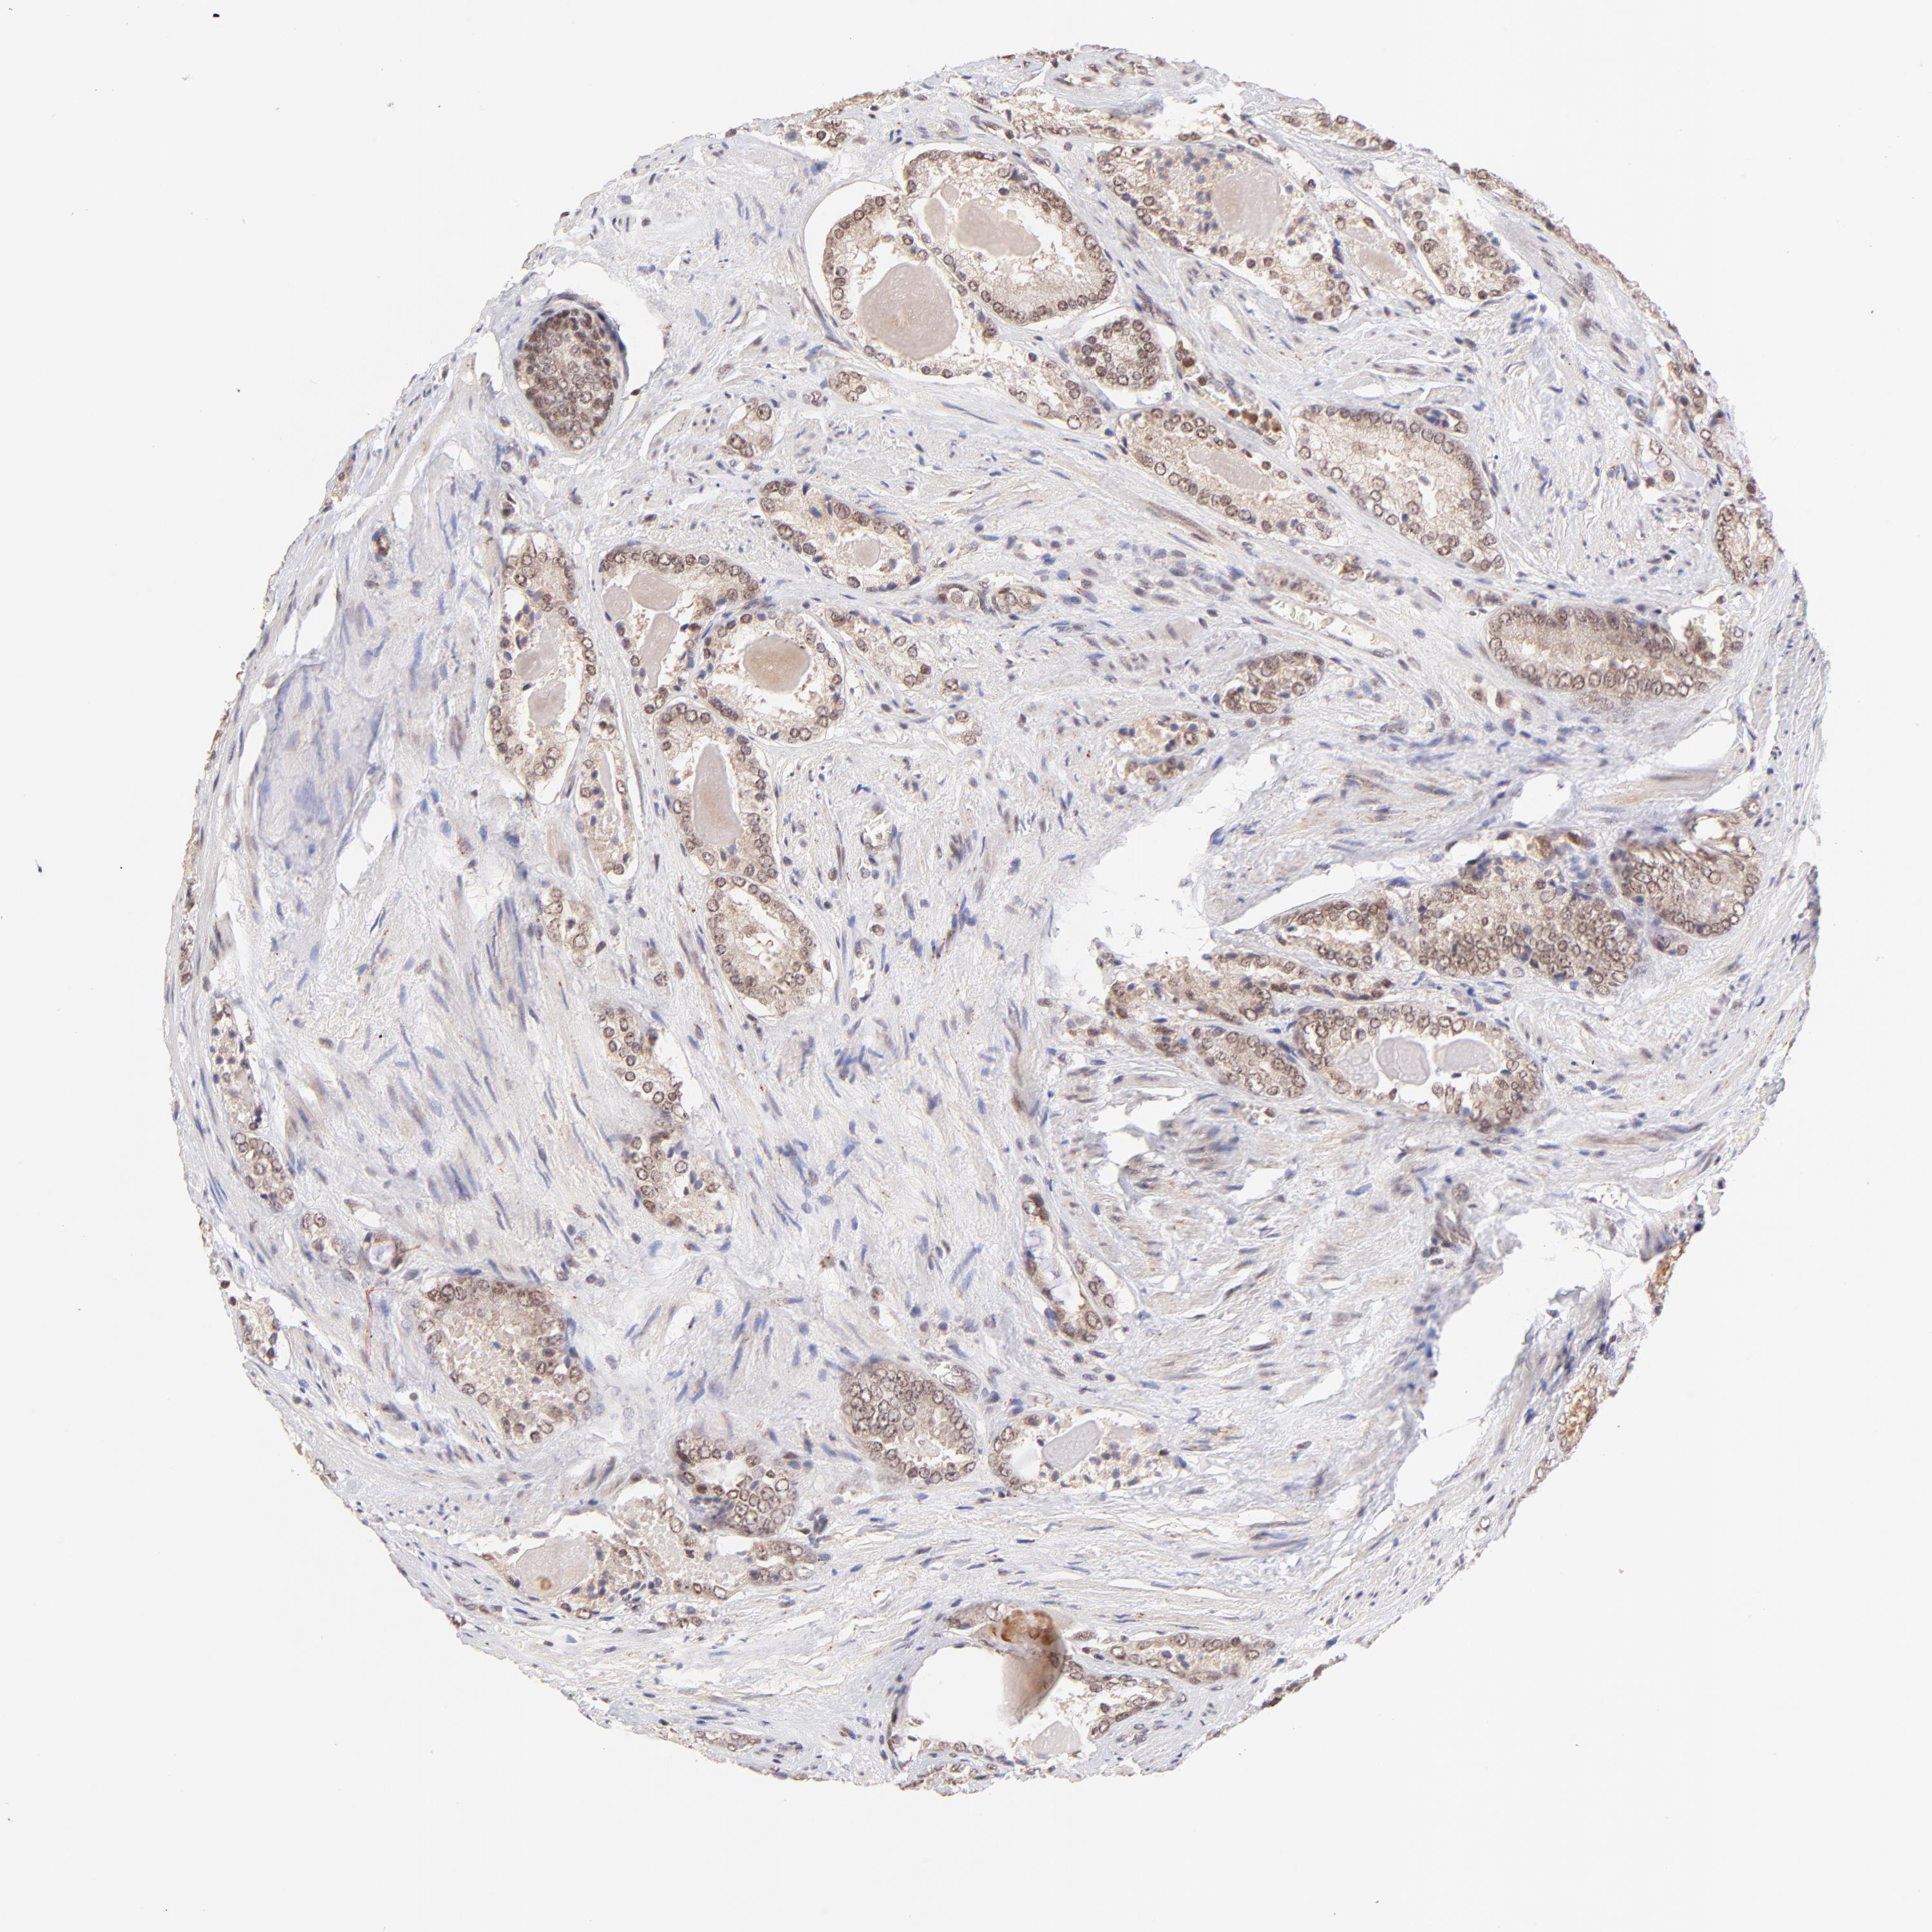

PROSTATE CANCER - Protein expressioni

A mouse-over function shows sample information and annotation data. Click on an image to view it in a full screen mode. Samples can be filtered based on level of antibody staining by selecting one or several of the following categories: high, medium, low and not detected. The assay and annotation is described here.

Antibody stainingi

Antibody staining in the annotated cell types in the current human tissue is reported as not detected, low, medium, or high, based on conventional immunohistochemistry profiling in selected tissues. This score is based on the combination of the staining intensity and fraction of stained cells.

Each image is clickable and will lead to virtual microscopy that enables deeper exploration of all samples and also displays staining intensity scores, fraction scores and subcellular localization as well as patient and tissue information for each sample.

Antibody HPA003184

Antibody HPA003185

Staining

High

Medium

Low

Not detected

Intensity

Strong

Moderate

Weak

Negative

Quantity

>75%

75%-25%

<25%

None

Location

Nuclear

Cytoplasmic/membranous

Cytoplasmic/membranous,nuclear

Adenocarcinoma, Low grade

Adenocarcinoma, Medium grade

Adenocarcinoma, High grade